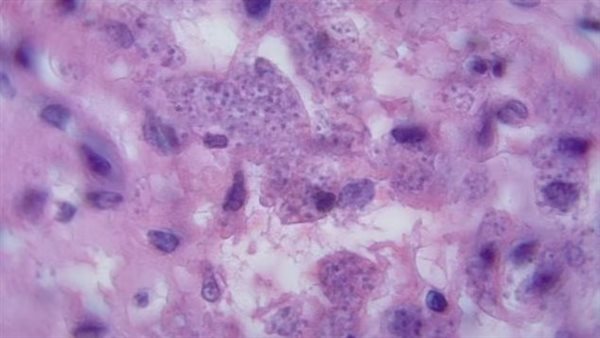

وتشمل هذه الأمراض داء الليشمانيات، وداء البلهارسيا، ومرض الأسطوانيات، التي تنتشر عن طريق لدغات الحشرات أو الديدان الطفيلية.

ويمكن أن تصيب هذه الحشرات الأعضاء، وتسبب أضرارًا طويلة المدى، وفي الحالات الشديدة تكون قاتلة.